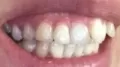

Мне 24 года. С 13-15 лет носила брекеты. В 19 прорезались зубы мудрости, и зубы верхней челюсти стали выступать из зубного ряда. Мучиться с брекетами больше не хочу.

Подскажите, есть ли ещё варианты исправления такой ситуации как у меня, хотя бы эстетически? Может виниры или элайнеры какие?

Конечно нельзя, проблема, действительно, связана с восьмыми зубами, которые необходимо удалить как можно раньше и после обратиться к ортодонту. К сожалению, выпирающий зуб настолько вылез из зубного ряда, что даже обточка и установка коронки в Вашем случае не дадут хороших результатов, да это и неправильно.

Так что выход один, хотите Вы или нет — брекеты!